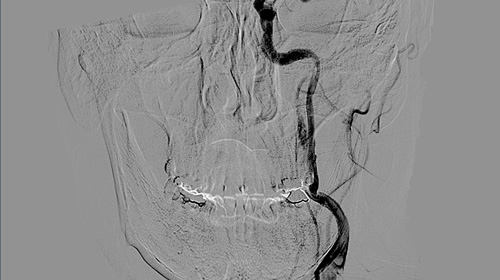

Head Neck tumors - When to think of malignancy

Head Neck tumor - any red flags?